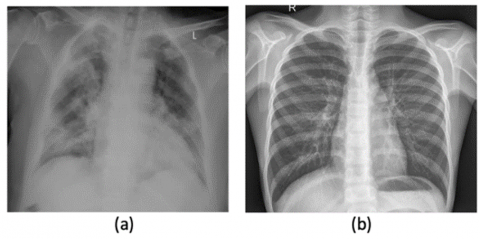

The most common image type (X-ray images) which is used in this study, which has been asked by most doctors for COVID-19 diagnosis as shown in Figure 2. This data set is available for public use in research, and researchers update it when more images are available to increase the data set size. Cohen et al. have developed this data set using different open-access sources [49, 50]. Figure 2 shows a sample from the used dataset.

Figure 2. X-ray chest images: a) COVID-19 defected lung b) Non-defected lung